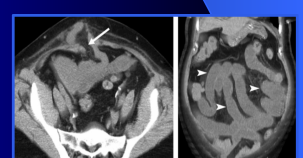

Hernies Obturatrices

- Femme agée et maigre

- Très rare

- CT Pathognomonique: Anse entre le muscle obturateur externe et le muscle pectiné